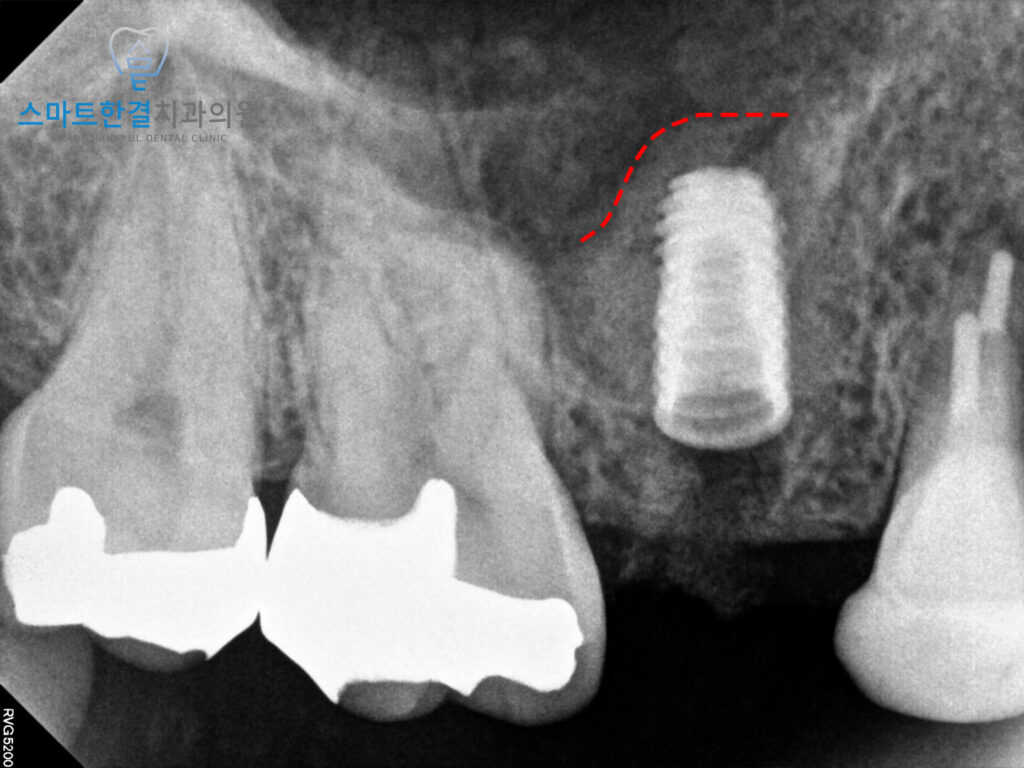

확인해 보니,

치아의 머리 부분만 부러져

잇몸 안에 뿌리만 남아 있는 상태였으며,

파절 범위가 깊어 치아를

보존하기 어려운 상황이었어요.

해당 부위는 상악동이 많이 내려와 있는 상태였고,

상악동의 영향으로 기존 치아의

뿌리 또한 옆으로 휘어 있는

형태를 보이고 있었어요.

이로 인해 발치 후 임플란트를 바로 식립하기에는

잇몸뼈의 높이가 충분하지 않아

안정적인 고정을 기대하기

어려운 상황이었는데요.